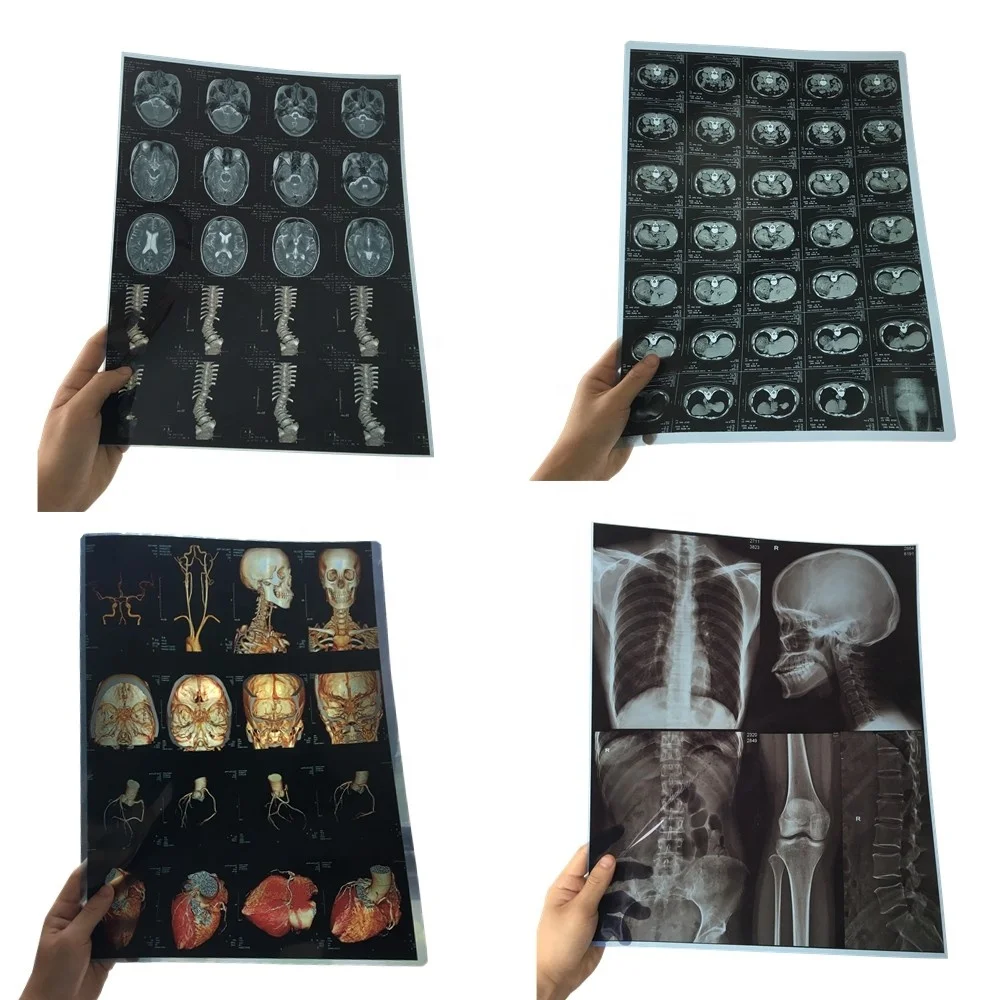

Лазерная камера сетевая для печати изображений на пленке стандарт dicom